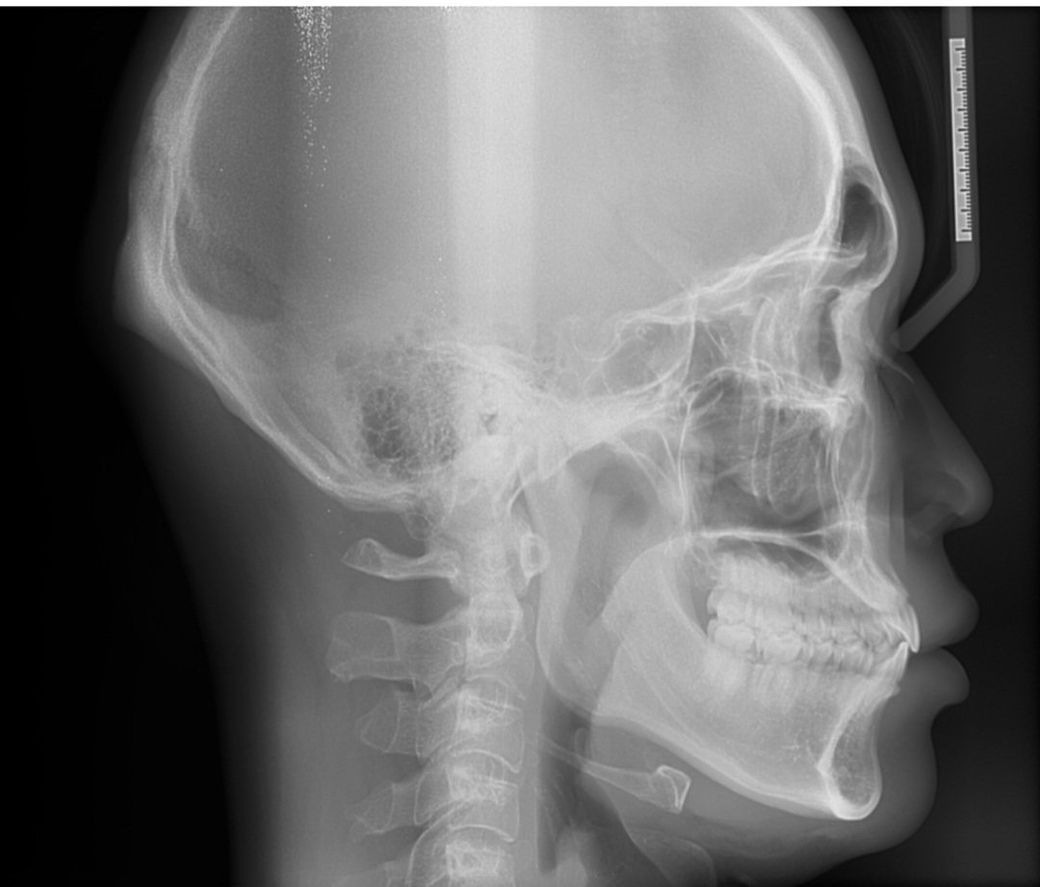

거북목은 귀의 중심이 어깨 위쪽 불룩한 부분을 기준으로 3cm보다 앞에 위치하면 거북목이라고 생각하시면 됩니다.

X-ray로 봤을때도 C자형 배열을 하지 않고 1자 또는 살짝 역C가 되어가고 있는 배열이 보입니다.